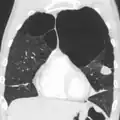

Pulmão com enfisema centrolobular característico do tabagismo. Este corte mostra múltiplas cavidades preenchidas por depósitos de carbono negro.

Microfotografia de um enfisema, em que se observa à esquerda grandes espaços vazios e à direita relativa conservação dos alvéolos.